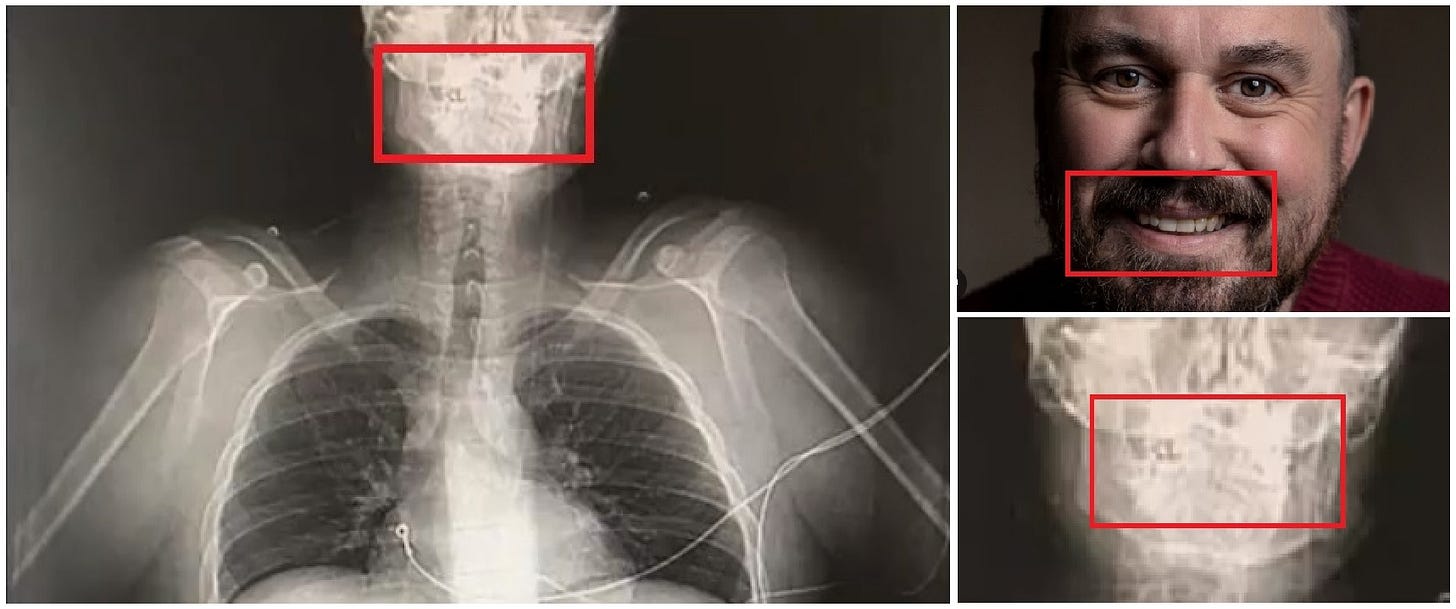

Strangely, although no such X-ray was contained in the medical evidence provided to the Court, one did appear in a LADbible report on the first anniversary of the Manchester Arena incident:

“Martin Hibbert,” reads the LADbible caption.

As Mark Conlon has pointed out, the teeth in the X-ray do not match those of Hibbert in photographs of him smiling.

Source: Mark Conlon

Yet, there is no obvious damage to the arms, throat, or jaw, or of shrapnel embedded in the face, in the above X ray. Nor is the image time-stamped, nor does it identify Martin Hibbert. Moreover, as Hall told the Court,

It cannot be deduced from the X ray, without a lateral view, whether the alleged shrapnel is inside the body, or not. The shrapnel could be on top of the body, underneath the body or possibly even using computer software.

In sum, there is no reason to trust the authenticity of the image.

Tellingly, the claimants did not enter the LADbible X-ray into evidence. They must have known that it would not withstand scrutiny. In which case, why did Martin Hibbert authorise its usage in the first place?